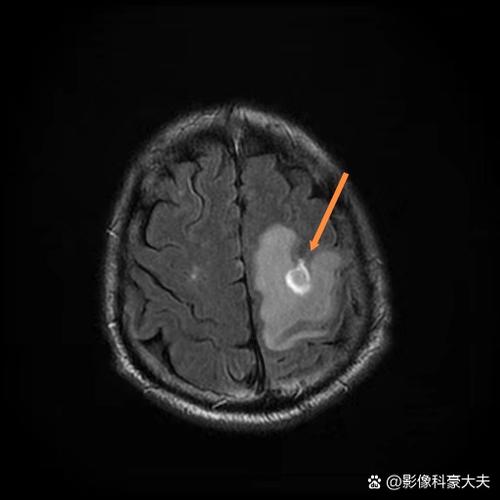

(图片来源网络,侵删)- 核磁: 可以在发病后30分钟到1小时内就发现脑梗死的迹象,它对早期细胞内的水分变化非常敏感,一旦脑细胞开始缺血坏死,DWI序列上就会显示出高信号(亮点)。